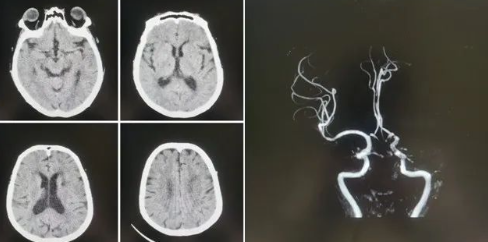

77歲的張阿姨(化名)家住公主嶺市劉房子街道,在活動中突發(fā)意識不清、言語不能,家屬在發(fā)病后1小時內緊急將患者送至我院急診。急診科醫(yī)生第一時間查看病人,患者高齡,進展性意識不清、言語不能,雙眼向左側凝視,壓眶疼痛刺激下左側肢體可抬起,右側肢體肌力0級,緊急啟動卒中救治綠色通道,立即進行頭CT檢查,排除出血后,考慮急性缺血性腦卒中,因患者發(fā)病時間短,緊急聯(lián)系卒中中心團隊,國文醫(yī)院卒中中心丁金明主任第一時間聯(lián)系影像科進行了頭部核磁血管檢查,確診為左側大腦中動脈急性閉塞。

緊急啟動導管室、麻醉科,在導管室、麻醉科人員的配合下在全麻下進行了腦血管造影術,造影顯示:III型弓,左側大腦中動脈M1段閉塞,余血管未見異常,立即進行左側大腦中動脈閉塞取栓術,因為患者III型弓,動脈硬化重,血管迂曲嚴重,在泥鰍導絲指引下,利用同軸技術(6F長鞘+5F多功能造影管)反復嘗試超選左側頸總動脈失敗。

在神經介入團隊丁金明主任、朱洪波副主任共同努力下,通過交換技術成功超遠目標血管,釋放取栓支架,通過取栓支架取出一團塊狀血栓,成功開通左側大腦中動脈血流,挽救了患者的生命,術后頭CT檢查未見出血,轉入重癥監(jiān)護病房進一步治療。